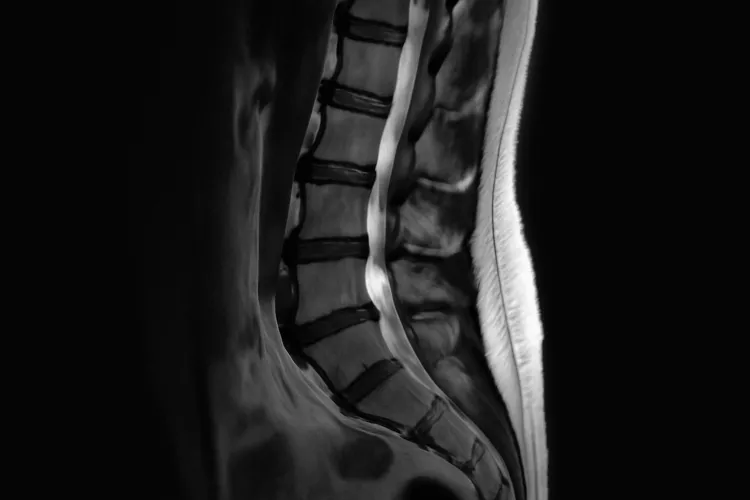

Вертеброгенный болевой синдром (ВБС) представляет собой сложное состояние, которое возникает из-за проблем с позвоночником. Этот синдром часто сопровождается сильной болью в области спины и может отдавать в конечности. Состояние возникает по разным причинам, включая дегенеративные изменения дисков и суставов, травмы, а также влияние постуральных нарушений. МРТ позвоночника является важным методом, позволяющим диагностировать источник боли и оценить состояние тканей.

Одним из ключевых методов диагностики является МРТ позвоночника. Этот метод позволяет получить четкие изображения тканей и структур позвоночника, что способствует выявлению межпозвонковых грыж, воспалений и других патологий. Кроме того, могут применяться рентгенография и КТ, которые помогают оценить состояние костной ткани.